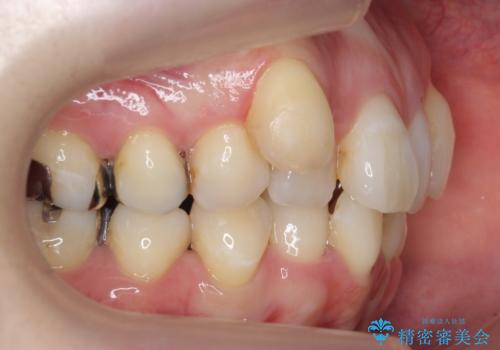

矯正治療後にしっかり全体の虫歯治療も行い、とても良い状態にできたと思います。

犬歯を抜いたとしても、矯正治療を短期間で終わらせて歯に負担がかからないようにし、虫歯治療その分しっかり行うのもメリットがあるのではないかと思います。

今回は特に左上の犬歯は歯肉退縮して根が露出していたのもあり、抜歯をお勧めしました。